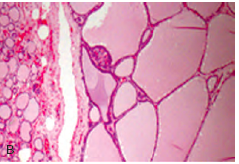

Thyroid gross

Thyroid histo

Histo: Colloid in the middle surrounded by follicular cells and C cells can be seen via IHC stain